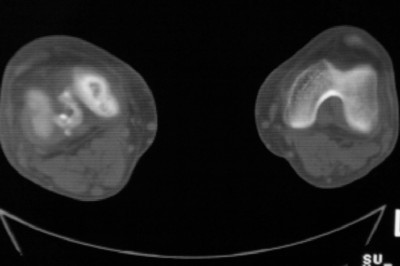

标题: CT8024:会诊!!!男 60 岁 双漆关节疼痛半年,进行性加重 [打印本页]

患者男 60 岁 双漆关节疼痛半年,进行性加重.

左侧股骨下端骨梗死

右股骨内髁关节面下多个不规则小囊变,边缘有明显硬化边,.......考虑: 1.关节面下骨囊变.  2.类风湿关节炎?   3.血友病?

右侧髁间隆突变尖,软骨下假囊肿形成,结合病人年龄较大,首先考虑退行性骨关节病。关节周围软组织未见明显异常,病人单单一双膝关节出现症状,不太支持类风湿性关节炎,可结合化验室检查。